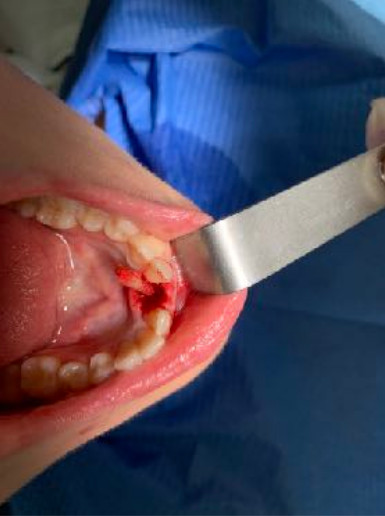

Il diametro ridotto del collo consente di mettersi al riparo da eventuali periimplantiti e migliora nettamente la velocità della guarigione. In questo caso è stato maschiato con un diametro 4 ed è stato inserito un impianto di Tramonte diametro 4 mm a 7 spire a collo corto . Il titanio utilizzato è sempre di grado 4.

| Sequenza frese: Solo fresa lanceolata | Sequenza maschiatori: maschiatore diametro 4 mm |

| Carico occlusale: immediato leggero. | |